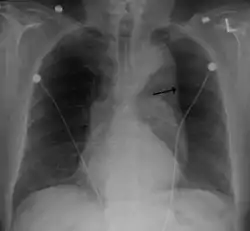

- Thoracic aortic aneurysm with arrow marking the lateral border of the aorta